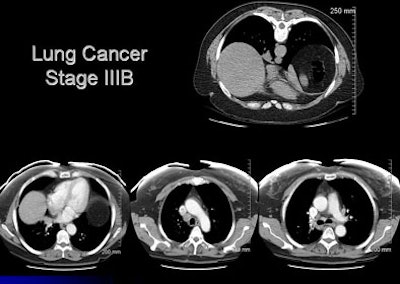

![]() |

| CT images of a 54-year-old woman revealed an opacity at the right lung base. The radiologist recommended a dedicated chest CT, which revealed abnormalities in the mediastinum; the patient subsequently underwent PET, and a biopsy confirmed lung cancer, stage IIIa. The patient was doing well following surgery, chemotherapy, and radiation. |